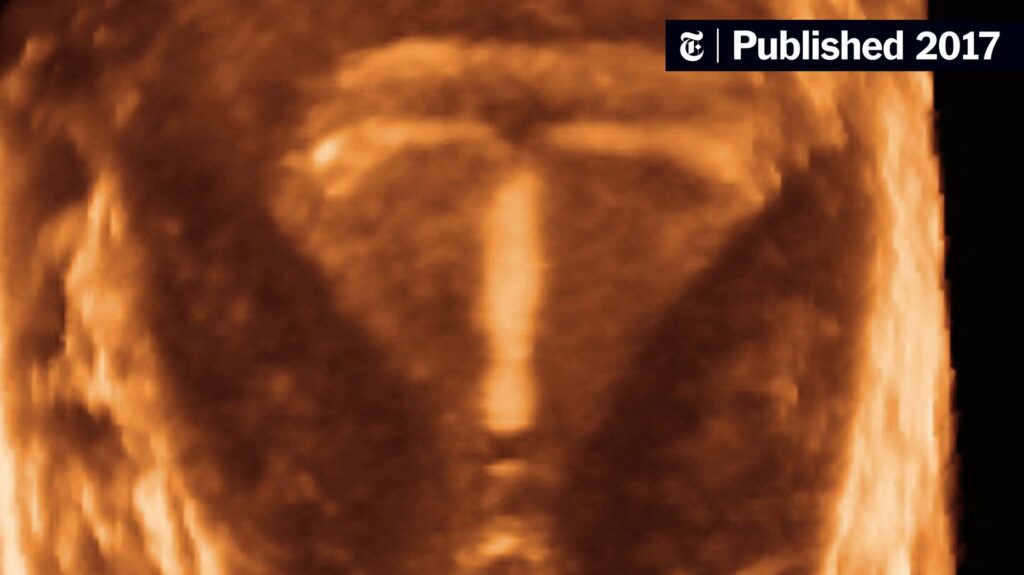

- Hormonspiral (IUS): F.eks. den levonorgestrel-frigørende spiral, der primært virker lokalt i livmoderen.

| Hormonspiral (Levonorgestrel) | ~1.21 | Selvom hormonet primært frigives lokalt, optages det systemisk i kroppen i tilstrækkelige mængder til at påvirke brystvævet. |

Ja. En af de bemærkelsesværdige opdagelser i studiet var, at den levonorgestrel-frigørende hormonspiral, som ofte opfattes som primært lokalt virkende, også var forbundet med en let øget risiko for brystkræft. Dette skyldes, at en del af hormonet absorberes i blodbanen og dermed når ud til resten af kroppen, inklusiv brystvævet.